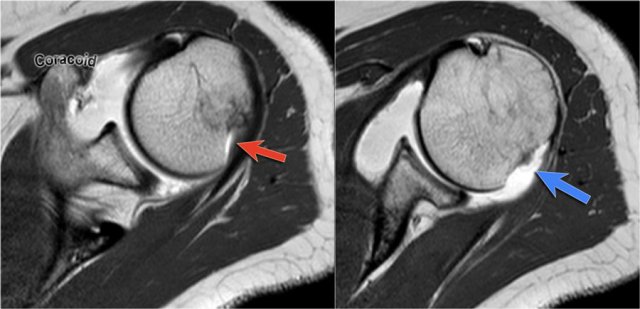

The MR-images are of a patient who had undergone both an anterior aswell as a posterior dislocation.

This resulted in both a Hill-Sachs impression fracture on the posterior aspect of the humeral head (blue arrow) and an impression fracture on the anterior aspect as a result of posterior dislocation (red arrow).